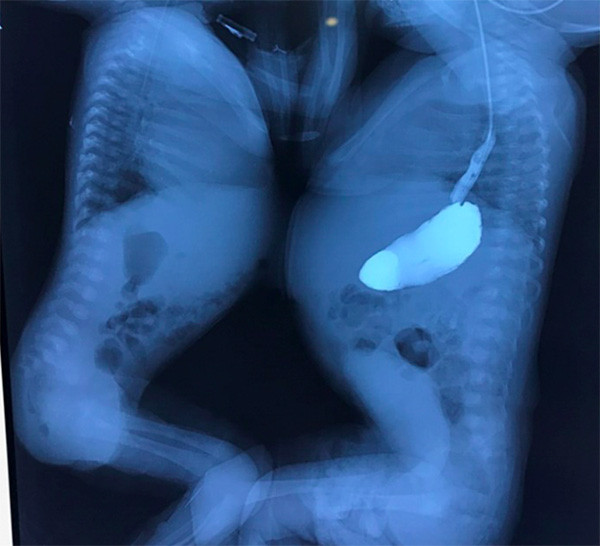

The two infants, V.N and V.T, were found to be conjoined twins when the mother was pregnant at 33 weeks. Local doctors performed a caesarean section seven weeks later, and the two babies were born weighing 2.2kg and 2.8kg respectively.

Meanwhile, V.N had respiratory failure and pustules all over the body. Through echocardiography, doctors of the Lao Cai provincial General Hospital found V.N also suffered atrioventricular septal defect.

Both babies were also found to have perihepatitis through abdominal ultrasound.

V.N suffered atrioventricular septal and single ventricle defects, severe atrioventricular valve regurgitation, aortic disruption, arterial inversion, and pulmonary atrophy.